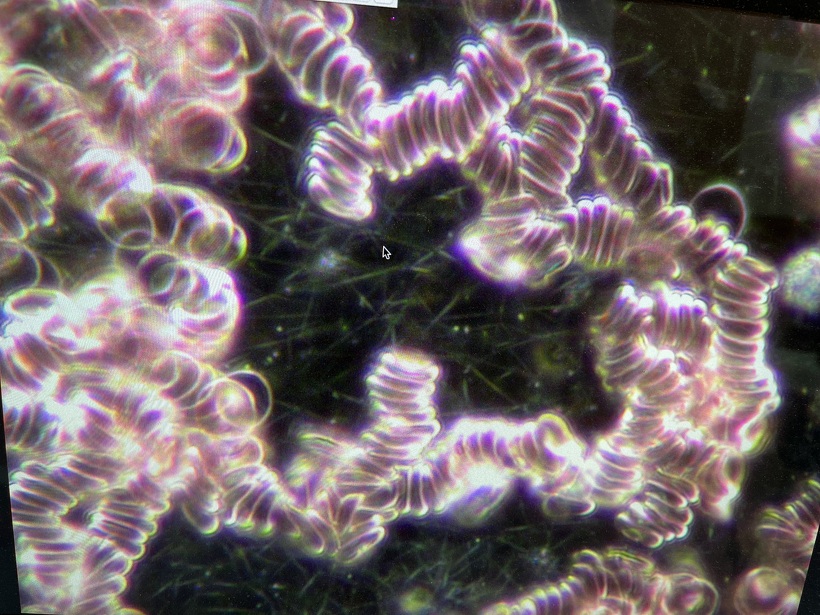

血液像 ドロドロ

写真2は血液中の赤血球像です。見事にドロドロです。食事指導の結果写真6のようにバラバラになりました。